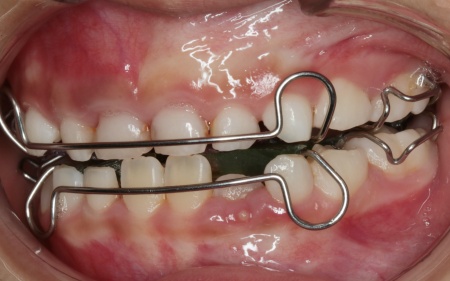

治療中

今回の治療では、床(しょう)矯正装置のひとつである「拡大床」という装置を使用した治療法をおすすめしました。

床矯正装置とは、プラスチックの土台部分がある取り外し式の矯正装置の総称です。拡大床は、そのなかでも顎の幅を拡大することを目的とした装置で、中央に組み込まれたスクリューと呼ばれるネジを少しずつ回すことで、顎の横幅を徐々に広げていきます。

まずは患者様専用の拡大床を製作し、装着を開始します。

治療中は、スクリューを少しずつ回すことで顎の骨が徐々に横方向に拡大されていき、永久歯が生えるためのスペースを十分に確保することができました。